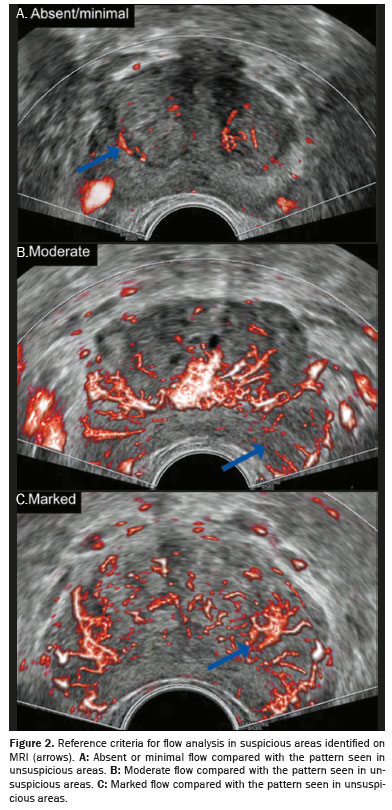

MATERIALS AND METHODS: This was a prospective cohort study including 88 patients evaluated between November 2023 and July 2024. We included men between 48 and 85 years of age with a prostate-specific antigen (PSA) level between 0.3 ng/mL and 21.0 ng/mL and an imaging finding with Prostate Imaging-Reporting and Data System (PI-RADS) category between 2 and 5. Patients with indeterminate biopsy results were excluded, as were those for whom PSA values were missing, those who did not undergo microvascular Doppler assessment, and those previously diagnosed with prostate cancer. In each case, we performed systematic 10-core transrectal biopsy, guided by 1.5-T magnetic resonance imaging–ultrasound fusion, as well as performing Doppler ultrasound with microvascular flow imaging. Vascularization was qualitatively assessed and categorized as absent/minimal, moderate, or marked. The Gleason score was classified as clinically significant (≥ 7) or not (≤ 6)..

Patients were placed in the left lateral position under anesthesia. Systematic biopsy was performed with 10 cores using an 18-G tru-cut needle via the transrectal route. The MRI scans (minimum 1.5-T) were fused with real-time ultrasound images acquired by using a high-resolution ultrasound system (RS85 Prestige; Samsung Medison Co Ltd, Seoul, South Korea). Microvascular Doppler ultrasound was applied to the MRI-identified suspicious area (Figure 1). All procedures were performed by an operator with over 15 years of experience.